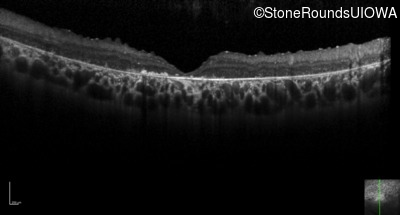

Optical Coherence Tomography - Right - 20/400 sc

Exemplar / OCT Stack